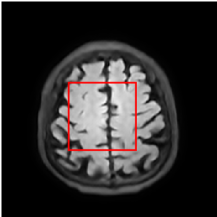

Figure 5 provides the qualitative comparison of the various methods on the four datasets at a scale of 4. The top, second, third, and bottom rows are the SR results under the FastMRI, clinical brain, clinical tumor and clinical pelvic datasets, respectively. The red boxes indicate the zoom-in region of complicated anatomical structures along with their corresponding error maps. Note that the brighter textures in the error maps, the lower the quality of the reconstructed images. As can be seen, compared to methods based on Transformers and CNNs, diffusion-based methods like DisC-Diff and DiffMSR (Ours) are capable of reconstructing high-realistic images with promising reconstruction metric scores (PSNR and SSIM). Nevertheless, while DisC-Diff can reconstruct high-precision MR images, it does not preserve the structure present in the original HR images, introducing some additional information that can affect medical diagnosis. In contrast, our method combines DM and PLWformer, which can preserve the original image’s structure while restoring high-frequency information.